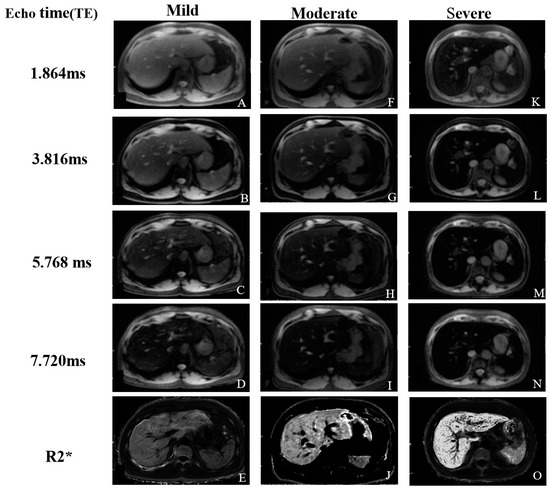

2.2.3. T2* and R2* Relaxometry

- Hankins, J.S.; McCarville, M.B.; Loeffler, R.B.; Smeltzer, M.P.; Onciu, M.; Hoffer, F.A.; Li, C.-S.; Wang, W.C.; Ware, R.E.; Hillenbrand, C.M. R2* magnetic resonance imaging of the liver in patients with iron overload. Blood 2009, 113, 4853–4855. [Google Scholar] [CrossRef]